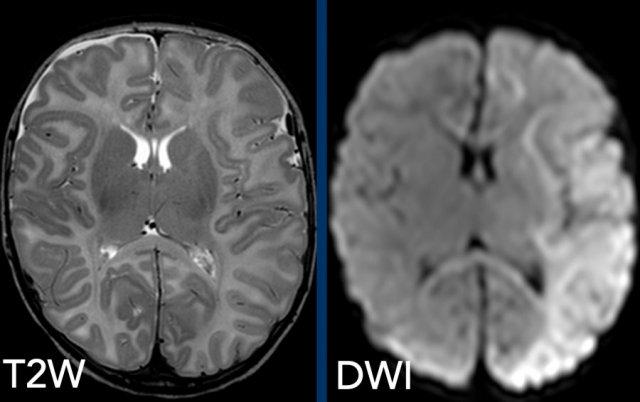

Các khiếm khuyết tưới máu là thành phần chính gây tổn thương lâu dài.

Do đó, chuỗi xung khuếch tán (DWI) cũng nên được đưa vào quy trình chụp MRI tiêu chuẩn.

Hình ảnh

Bé trai 2 tháng tuổi với gãy bong điểm bám sụn-xương vùng hành xương, gãy xương sườn và co giật. Chuỗi xung T2W cho thấy ổ dịch dưới màng cứng vùng trán phải khó nhận thấy, nhưng hạn chế khuếch tán lan rộng được ghi nhận rõ ràng trên DWI.